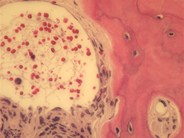

Primary myelofibrosis - fibrotic stage

Bone marrow biopsy shows severe marrow fibrosis with osteosclerosis